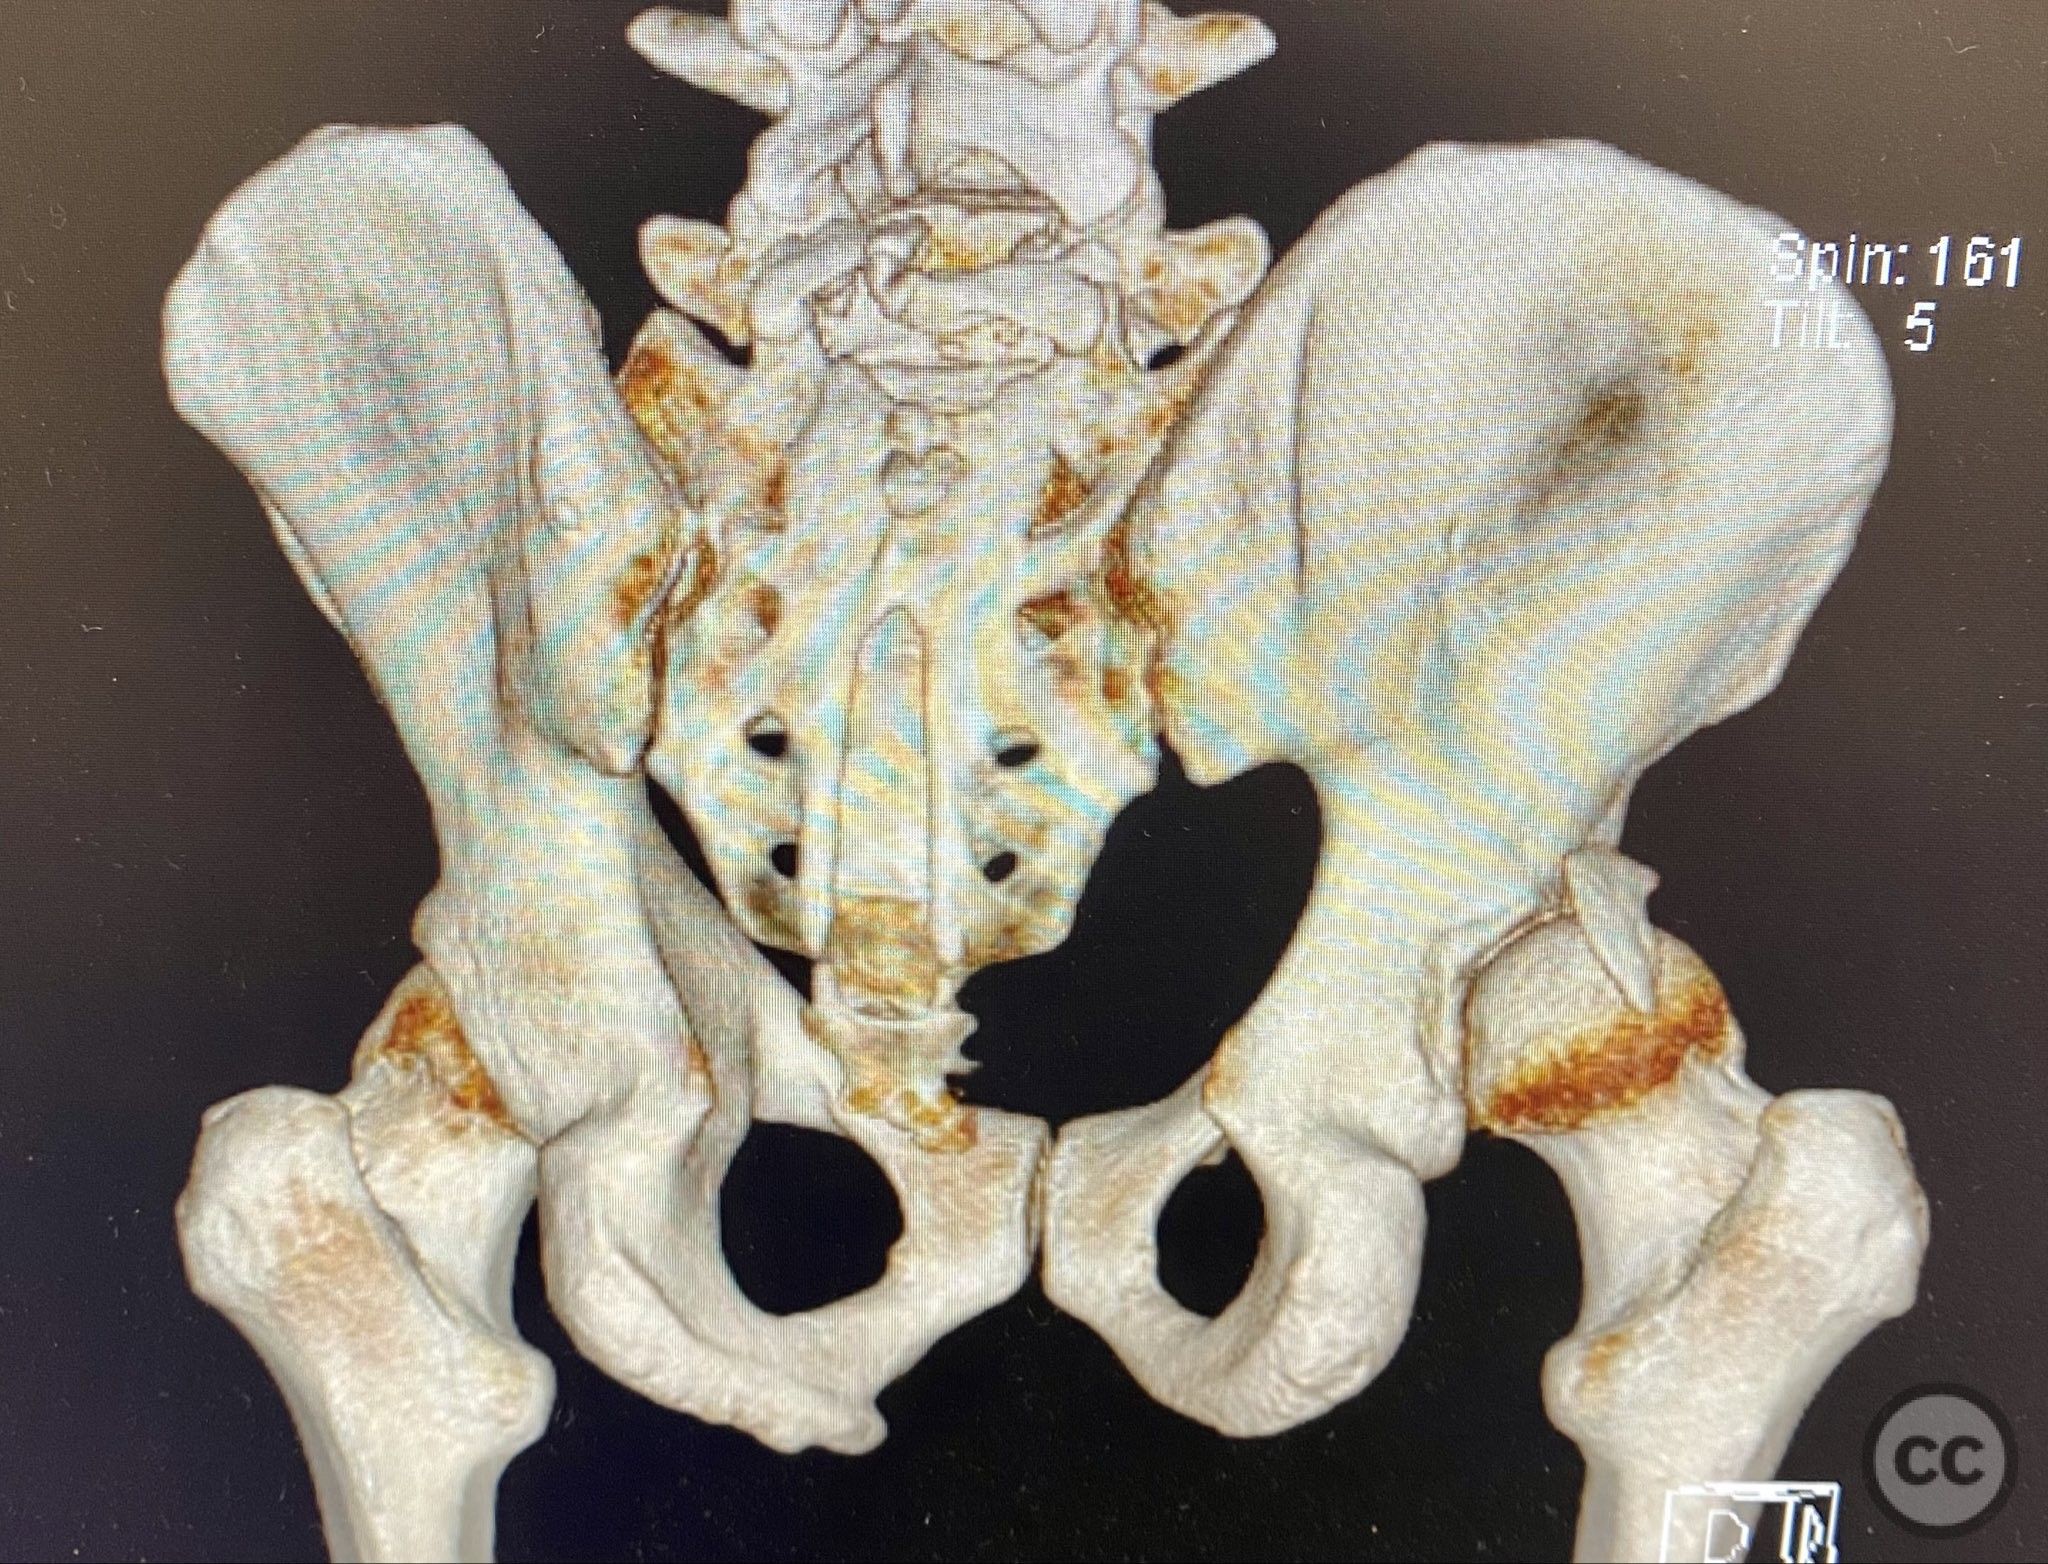

Clinical and radiological findings:  A middle-aged patient sustained a posterior wall acetabular fracture-dislocation, as demonstrated on initial AP pelvic radiograph. The film revealed a sizeable posterior wall fragment, cranial lateral impaction of the acetabular dome, and subtle deformation of the femoral head contour. Neurovascular examination was performed, including assessment of distal pulses and sciatic nerve function. The ipsilateral knee and anterior chest were examined for associated injuries (including possible knee ligamentous injury and thoracic trauma). An initial attempt at closed reduction under sedation was unsuccessful.

Planning remarks:  The preoperative plan included advanced imaging with CT, including 3D surface renderings, to further delineate the extent of articular impaction, wall fragment size, and comminution. The plan was for open reduction and internal fixation via a posterior Kocher-Langenbeck approach in the prone position. Elevation of impacted articular segments was planned, with structural support using autologous bone graft harvested from the greater trochanter. Fragment-specific fixation was planned with a spring hook plate for the cranial wall fragment and a reconstruction plate for the main posterior wall fragment.

The initial failed closed reduction likely resulted from interposed soft tissue or bony fragments, or inadequate sedation/muscle relaxation. Repeat reduction under improved conditions was successful prior to definitive fixation. 3D CT renderings provided enhanced visualization of impaction zones and comminution, facilitating preoperative planning for grafting and fragment-specific fixation. Intraoperatively, elevation of the impacted dome required careful manipulation to avoid further chondral injury. Use of a spring hook plate provided secure fixation of the cranial wall fragment, while the reconstruction plate supported the main wall fragment. Postoperative CT confirmed satisfactory reduction and implant positioning.